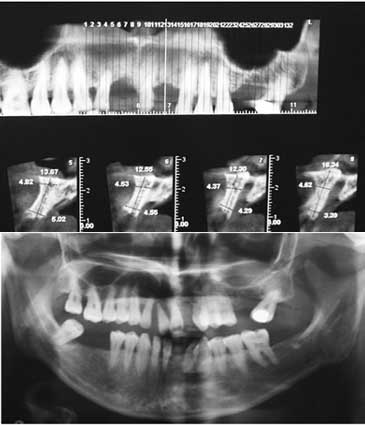

The study was approved by the Ethics Committee of Mashhad University of Medical Sciences (MUMS) and was registered in the Iranian Registry of Clinical Trials (IRCT) database (IRCT num.: IRCT138812081601N2). Twelve female patients, 30‒60 years of age, with insufficient ridge width, were included in this clinical trial and informed consent was obtained from all the patients. In all the cases, bone grafting was needed in the anterior and premolar region to restore natural ridge contour to support an implant. All the patients had ridge widths measuring ≤3 mm, which would be amenable only to block grafting procedures rather than particulate grafts. Figure 1 shows preoperative radiographs of one of the patients. Patients' systemic health was good and there were no contraindications for surgical placement of implants. The exclusion criteria were limited to systemic conditions such as bisphosphonate use, which contraindicate surgical implant treatment. Two days prior to the surgery, a ten-day regimen of co-amoxiclav (625 mg) was administered. The patients were instructed to use chlorhexidine mouthwash 0.2% just before the operation. Under local anesthesia, a mucoperiosteal flap was elevated to clearly expose the ridge defect. Using a gauge, the width of the residual ridge was measured in its thinnest portion and then, several perforations were made into the cortical bone by a round bur (Figure 2).

Figure 1.Preoperative radiographs.